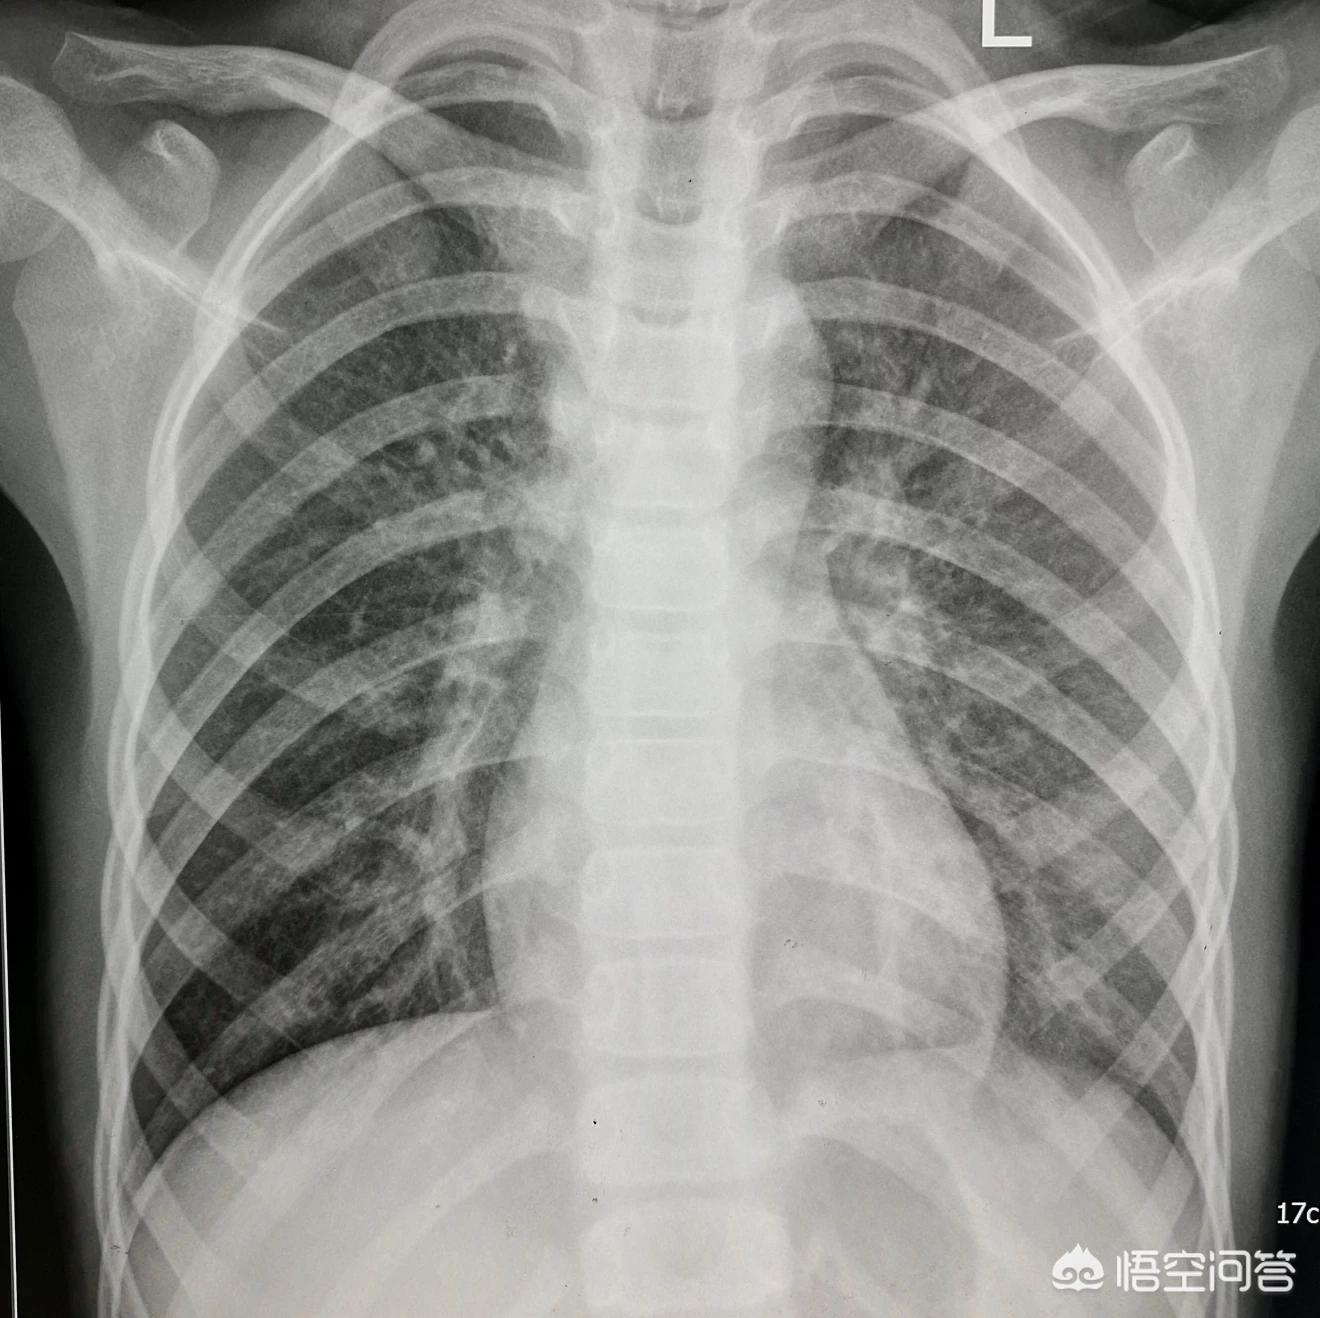

先来看一张小儿肺炎治疗前后对比的图像:典型的小儿肺炎,治疗一周后复查胸片。 可以看到左上肺的大片炎症,抗炎治疗一周后明显吸收消散。宝宝如果出现了明显高热,持续的咳嗽咳痰一定要及时就诊,防止发生大叶性肺炎,继发其他系统的问题。